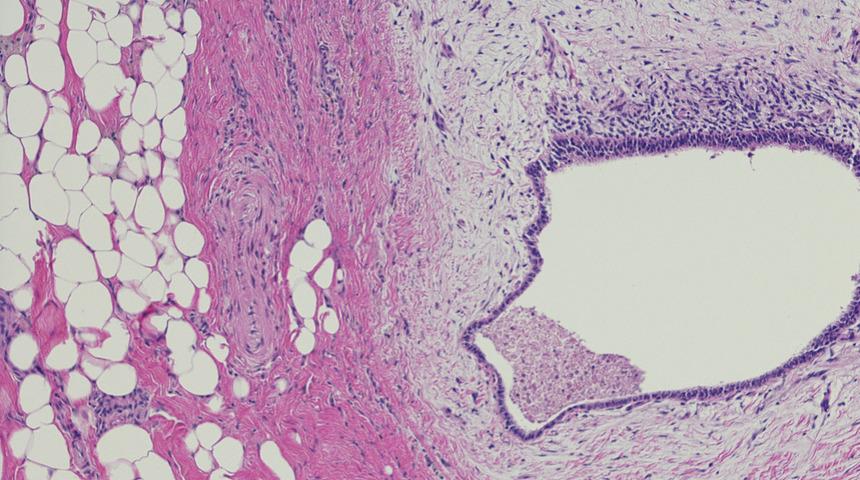

Özlem Türe’yi sağlığına kavuşturmanın ötesinde adeta yeniden hayata gelmiş gibi hissettiren Kadın Hastalıkları ve Doğum Uzmanı Prof. Dr. Taner Usta da genç kadının hastalığını şöyle anlatıyor: “Özlem hanımın hastalığı siyatik sinir endometriozisiydi. Yani çikolata kisti hastalığının leğen kemiğinin içinden geçen siniri tutan nadir bir formu. Derin Endometriozis olarak da adlandırılan, yumurtalığın dışındaki doku ve organları tutabilen formun nadir bir türü. Hastalığı diğer jinekolojik muayenelerden farklı olan özel bir muayene yöntemi ve ayrıntılı tetkiklerle teşhis ettik.”

Özlem Türe’nin, ülkemizde tedavisi yapılan ilk siyatik sinir endometriozis'i hastası olduğunu belirten Prof. Dr. Taner Usta “Siyatik siniri tutan derin endometriozisi 4,5 saat süren zorlu bir ameliyatla, üç boyutlu laparoskopik yöntemle cerrahi olarak çıkardık ve sinirin üzerini tamamen temizledik. Dolayısıyla siyatik sinir endometriozis'i doğru tanı ve tedavi ile rahatlıkla tedavi edilebilir bir hastalıktır.” diyor.

Halk arasında ‘çikolata kisti’ olarak bilinen ve kadınların en sık karşılaştığı jinekolojik hastalıklardan biri olan endometriozis, rahmin içini dolduran doku tabakasına ait hücrelerin, yumurtalıklar, bağırsaklar ve mesane gibi rahim dışında başka bir organda yerleşip büyümesiyle ortaya çıkıyor. Bu sinsi hastalık, çok farklı şikayetlere yol açtığından teşhisi yıllarca konulamayabiliyor. Tek başına bel ağrısıyla kendini gösterebildiği gibi, sürekli yorgunluk, gaz ve şişkinlik, idrarda yanma, şiddetli adet sancıları hatta depresyon gibi birbirinden çok farklı maskelere bürünebiliyor. Acıbadem Altunizade Hastanesi Kadın Hastalıkları ve Doğum Uzmanı Prof. Dr. Taner Usta, iyi huylu ama kötü davranışlı olan, isminin aksine kişiye hayatı zehir edebilen çikolata kistinin, etraftaki idrar yollarına giden borucuğu daraltarak sessiz böbrek kayıplarına bile yol açabildiğini belirtiyor. Bilimsel çalışmalar endometriozise tam olarak neyin neden olduğunu henüz ortaya koyamasa da, çevresel faktörler ve kimyasalların da bu hastalığa zemin hazırladığı tahmin ediliyor.